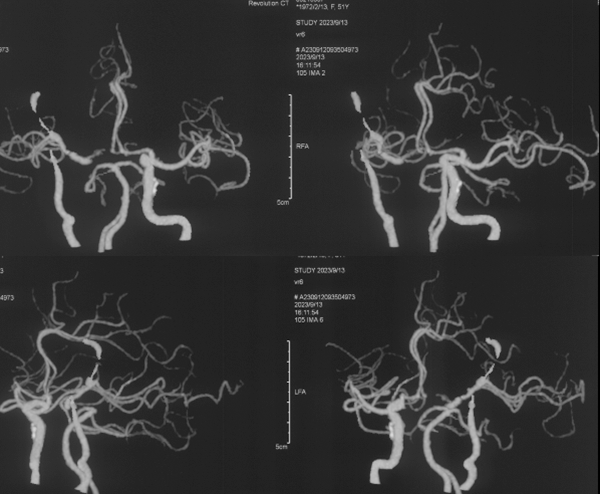

3. 脑血管造影示:右侧颈内动脉床突段和床突上端血管不均匀狭窄,向内侧上方移位,后交通、前交通不开放,大脑中动脉供血区域血管分布较少;椎基底动脉无明显皮层吻合向右侧大脑半球供血;左侧大脑前动脉双干。

术后CTA

桥血管通畅